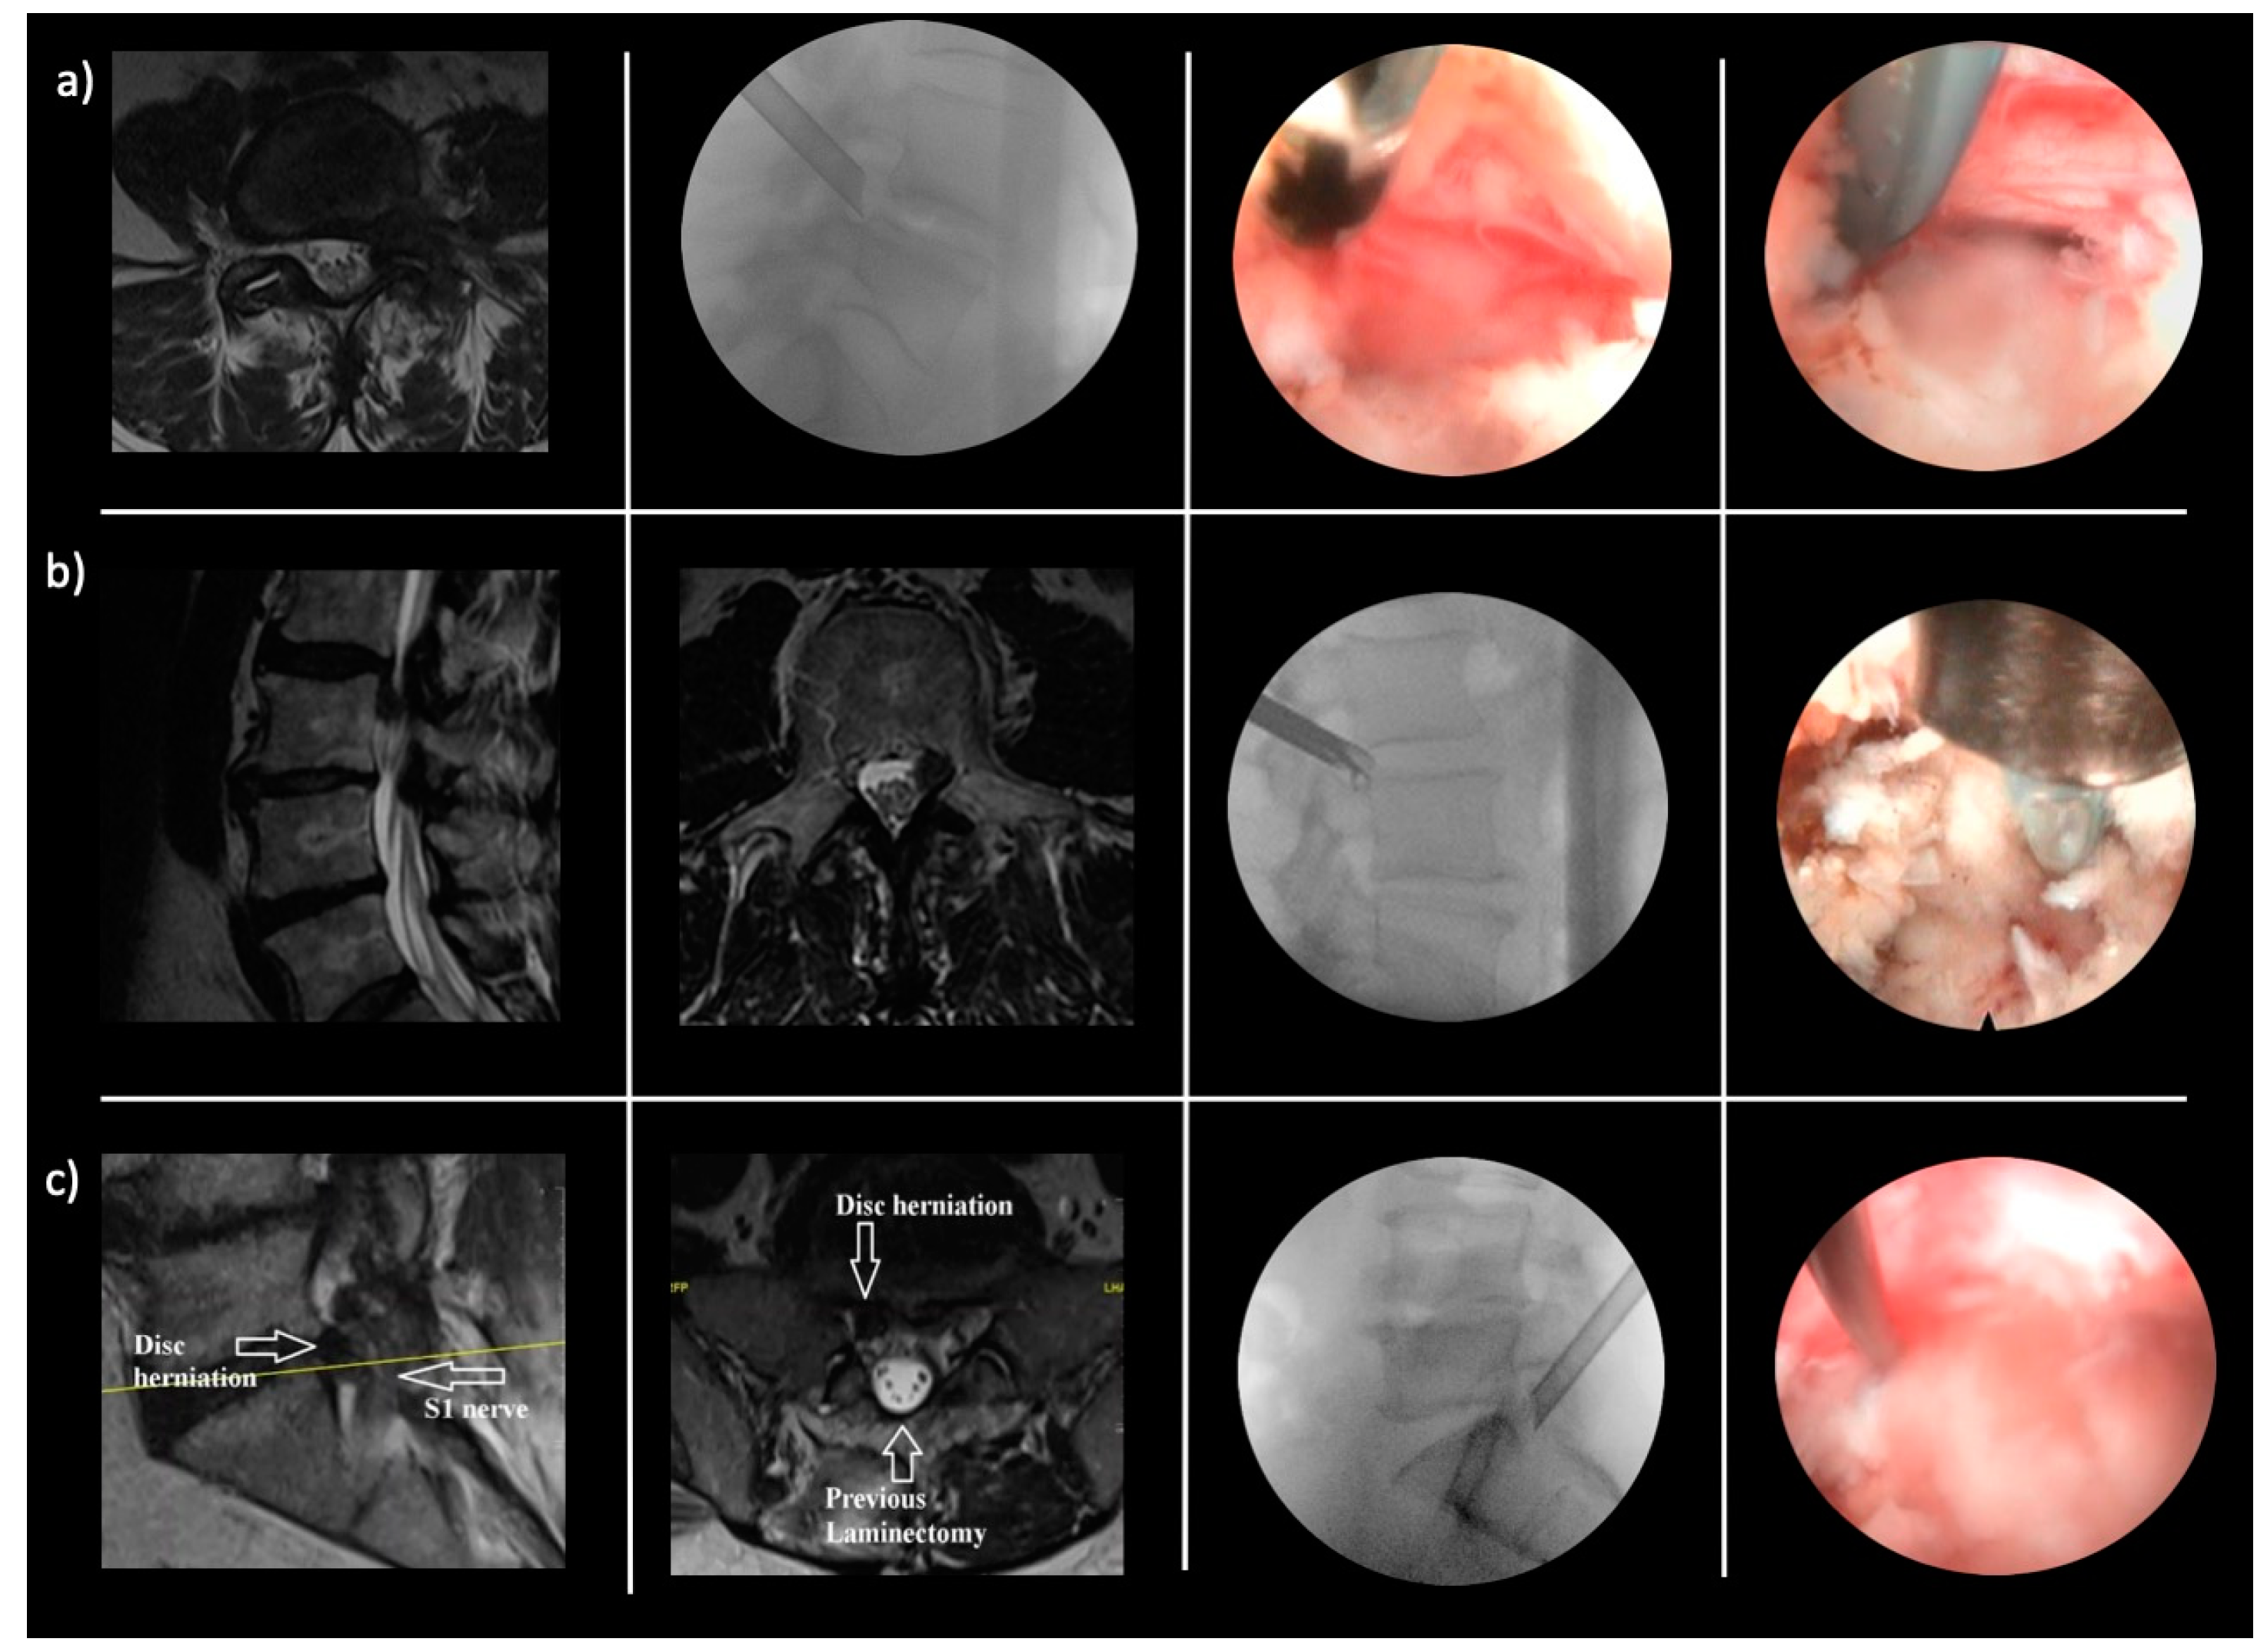

- Lewandrowski, K.-U.; Abraham, I.; León, J.F.R.; Telfeian, A.E.; Lorio, M.P.; Hellinger, S.; Knight, M.; De Carvalho, P.S.T.; Ramos, M.R.F.; Dowling, Á.; et al. A Proposed Personalized Spine Care Protocol (SpineScreen) to Treat Visualized Pain Generators: An Illustrative Study Comparing Clinical Outcomes and Postoperative Reoperations between Targeted Endoscopic Lumbar Decompression Surgery, Minimally Invasive TLIF and Open Laminectomy. J. Pers. Med. 2022, 12, 1065. [Google Scholar] [CrossRef]

- Yeung, A.; Roberts, A.; Zhu, L.; Qi, L.; Zhang, J.; Lewandrowski, K.-U. Treatment of Soft Tissue and Bony Spinal Stenosis by a Visualized Endoscopic Transforaminal Technique Under Local Anesthesia. Neurospine 2019, 16, 52–62. [Google Scholar] [CrossRef]

- Lewandrowski, K.-U.; Yeung, A. Lumbar Endoscopic Bony and Soft Tissue Decompression With the Hybridized Inside-Out Approach: A Review And Technical Note. Neurospine 2020, 17, S34–S43. [Google Scholar] [CrossRef] [PubMed]

- Yeung, A.; Lewandrowski, K.-U. Early and staged endoscopic management of common pain generators in the spine. J. Spine Surg. 2020, 6, S1–S5. [Google Scholar] [CrossRef] [PubMed]